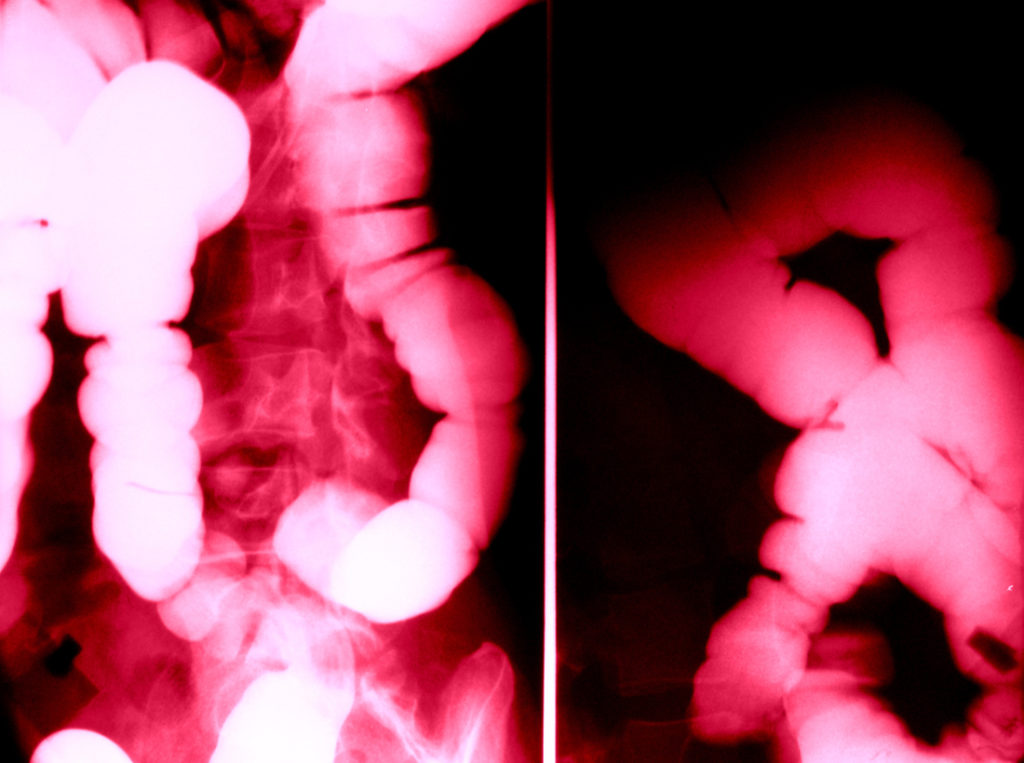

『便秘と宿便』断食博士の解説

突然ですが、いくつか質問をさせてください。Q.今は、どんなことを感じていますか?①家族のことですか?②仕事のことでしょうか?③または、健康のことですか?Q.今、悩んでいること…